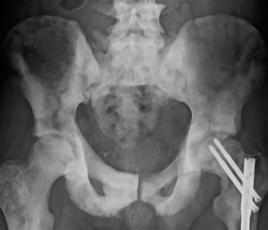

3.骨髓穿刺多次“乾抽”或呈“增生低下”;